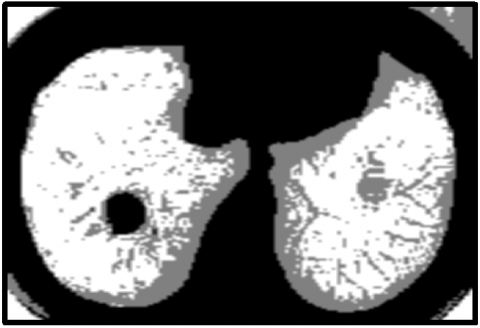

For clustering the input image, the KWFLICM algorithm is applied. After that, the tumor region is separated from the clustered output of the KWFLICM method using the histogram approach. When it comes to clustering results, the KWFLICM method performs faster than other FLICM algorithms and produces superior results when images contain outliers or salt and pepper noise. The KWFLICM segmentation and clustering image is displayed in Figure 8.

(a)

(b)

Figure 8. (a) KWFLICM clustered image; (b) segmented image